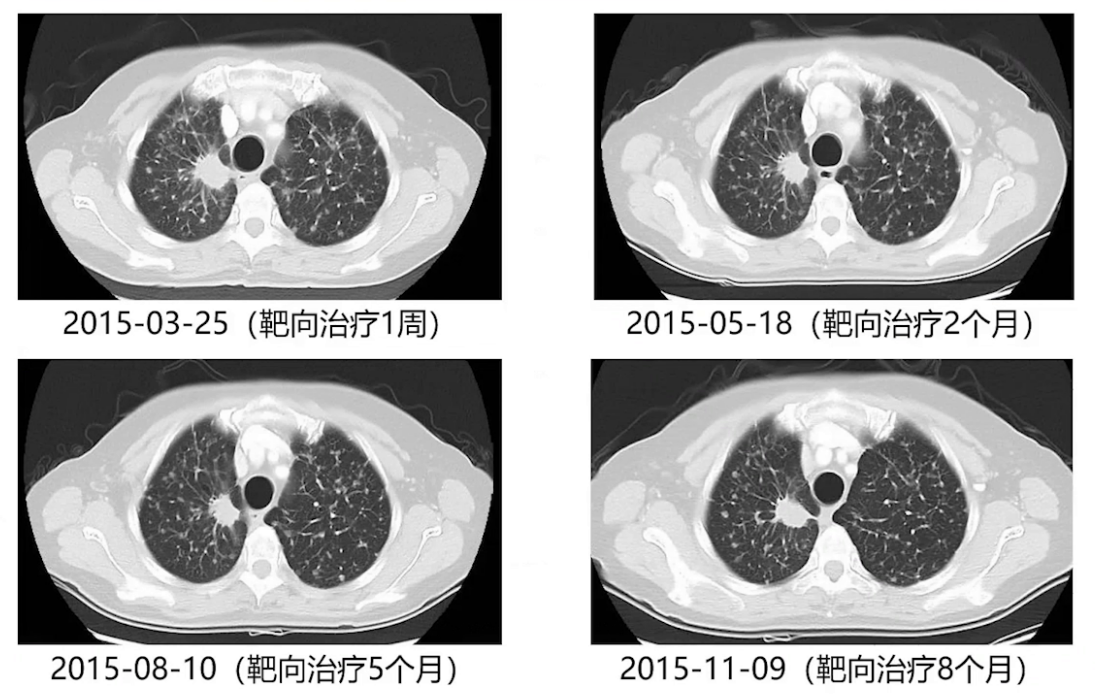

2015年3月18日患者开始口服阿来替尼进行靶向治疗,1周后一般状况明显改善,可独立行走,复查胸部CT示双肺弥漫结节有所缓解;2个月后复查,双肺弥漫结节仍在缓解,但右肺上叶肿物变化不明显,处于稳定状态。

2015年11月完善全身评估后,12月3日行胸腔镜下右肺上叶切除术,术后病理见少量腺癌残留(约10%),瘤床内肿瘤大部分变性坏死、间质纤维化及泡沫样组织细胞浸润。术后继续厄洛替尼靶向治疗。